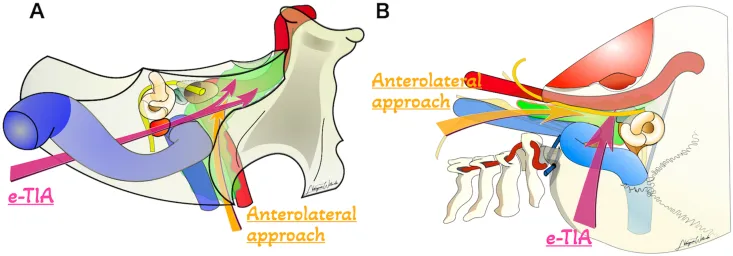

一位61岁的男性患者就遭遇了这种情况——他的舌头已经出现中度萎缩,影像检查显示肿瘤从扩大的舌下神经管一路延伸,向上侵及脑干周围的硬膜内空间,向下则蔓延至高位颈椎区域。...

累及或延伸至岩骨的病变,由于位置深在、解剖结构复杂,手术挑战巨大。复杂的颈静脉孔区肿瘤,如较大的软骨肉瘤,可向前、向上延伸至岩尖。...